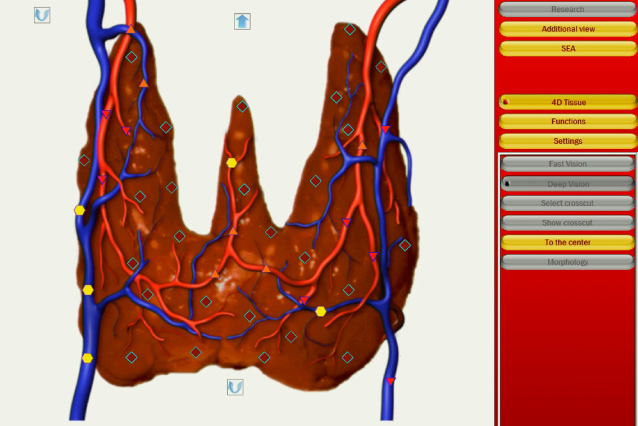

全身の各器官を状態によって6段階で評価します。

筋肉、肝臓、心臓、脳などの臓器はもちろんのこと、もう少し細かい細胞や神経、血管まで測定が可能です。

上図のように各組織ごとに評価し、数値として可視化されます。